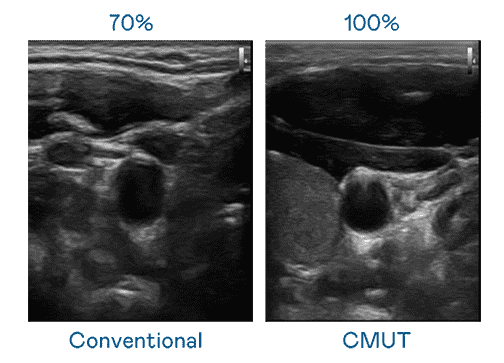

CMUT 技术是一种用电容式微机电元件来产生超音波讯号的技术。。。与传统 PZT 压电式技术相比,,,CMUT 频宽增加 30%,,,更宽频的超音波讯号让影像解析度大幅提升,,是实现高影像品质医疗超音波扫描、、、、促进精准医疗发展的关键技术。。。

大频宽带来超清晰影像

超音波影像的解析度高低,,首先取决于探头能发出的讯号频宽。。。28国际 CMUT 可提供高清晰的超音波讯号,,,提供高频宽、、高灵敏度、、、影像纹理细节更高的超音波影像,,,,协助医护人员缩短影像判读时间及利用精准的医疗影像进行诊断。。。